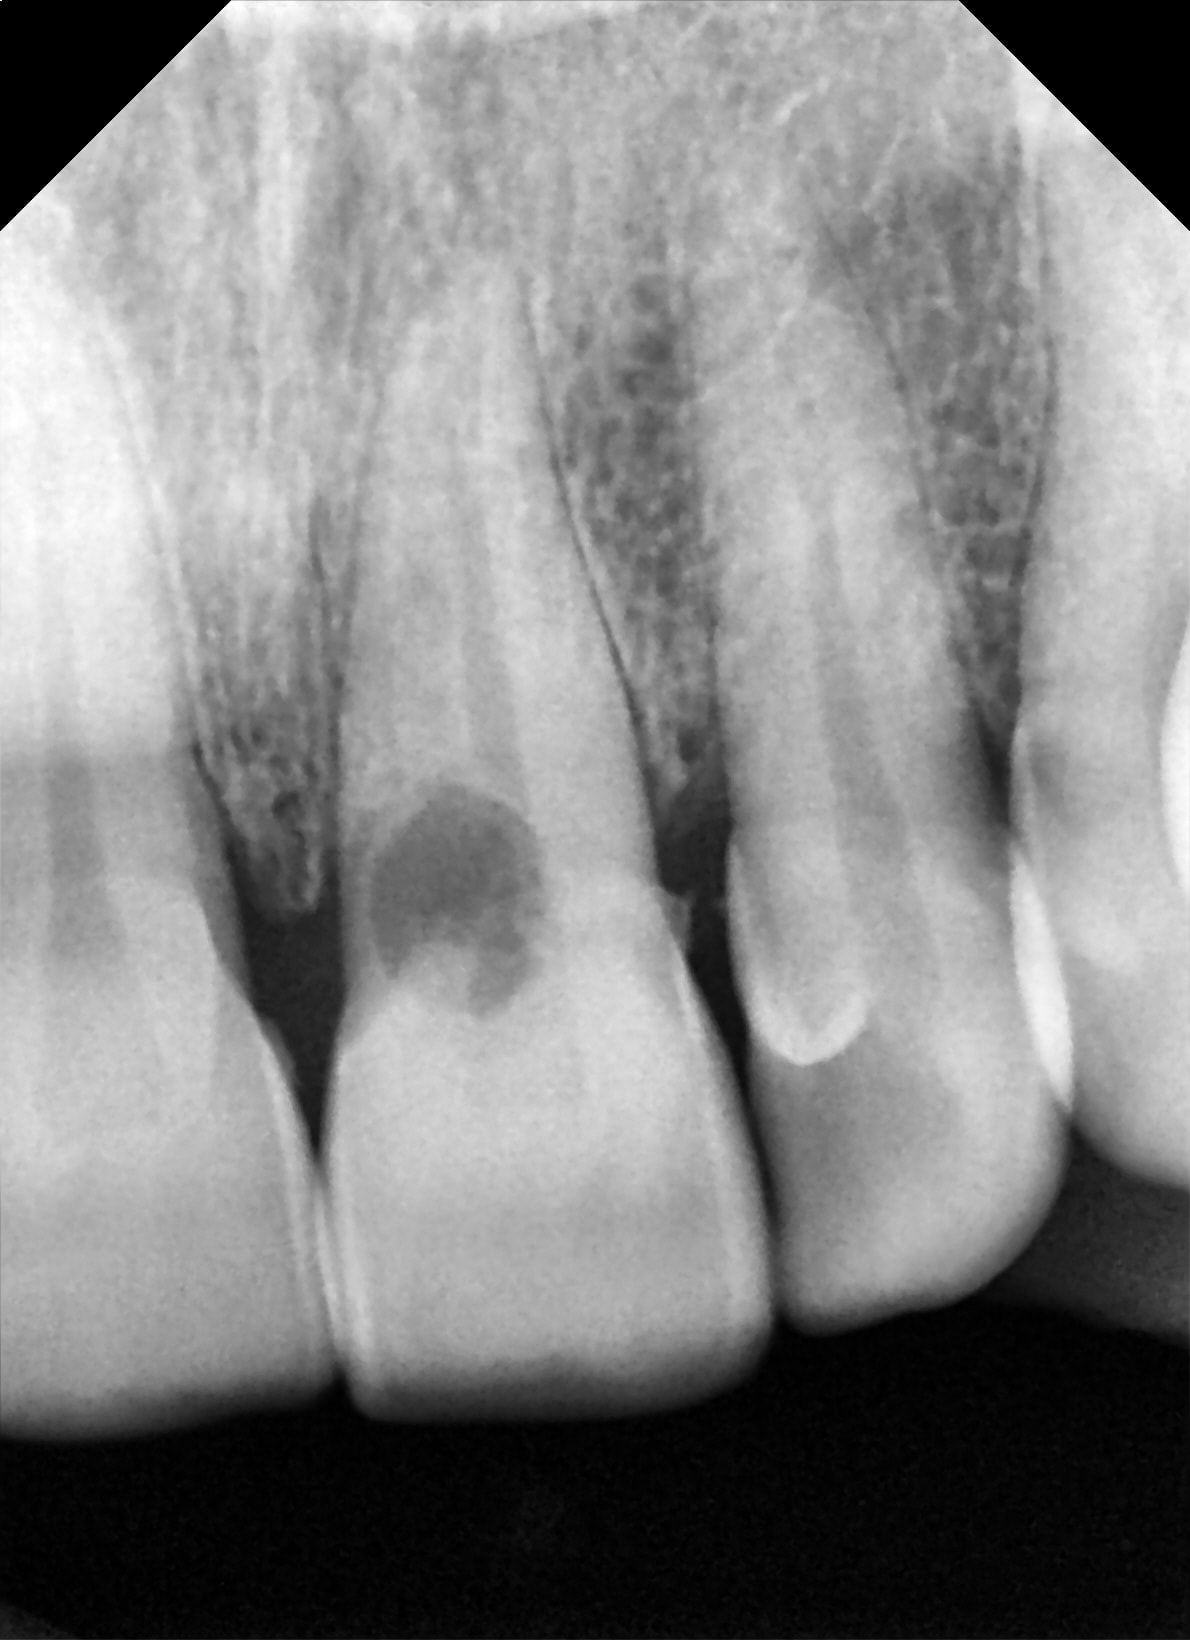

Pour la 11 ça a pas fonctionné:-(

C'est la même 11, j'ai pas mis la RX dans le bon sens.